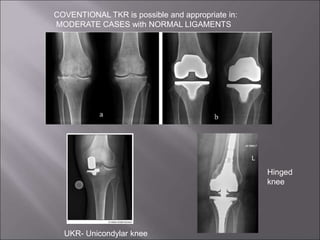

COVENTIONAL TKR is possible and appropriate in:

MODERATE CASES with NORMAL LIGAMENTS

UKR- Unicondylar knee

Hinged

knee

• Used when the knee is highly unstable : the person's

ligaments unable to maintain stability

• Severely damaged knees

• The two metalic pieces are connected with a hinge-like

device that keeps the joint in-line & support proper

alignment for function.

– Though It doesn’t last as long as the other knee

replacements

 It is performed if the damage is limited to one

side of the joint only with the remaining part of

the knee joint being relatively spared

 The incision is only three inches compared to 8

inches for a total knee replacement

 Less invasive and more successful